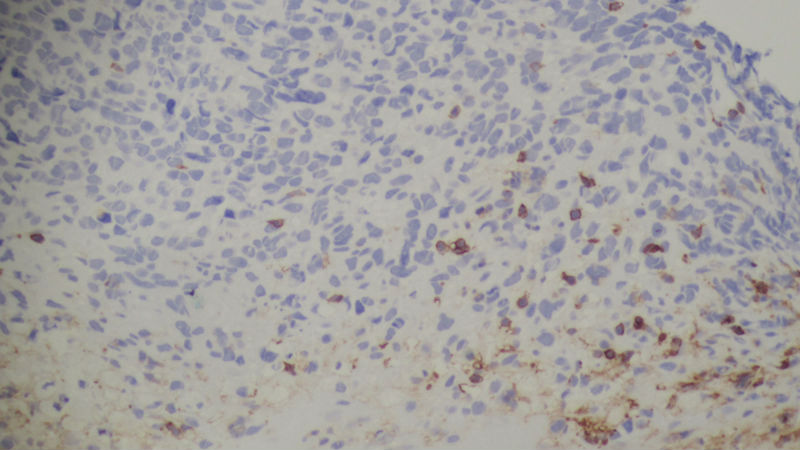

患者男性,47岁,胃部不适三月余,胃镜示:胃窦部1x1.2cm不规则隆起。

谢谢大家的讨论,这例我在标记胃部肿瘤时S-100蛋白是(-)而原发灶S-100(+),我在想,是否免疫标记缺失,同时转移灶中色素几乎没有形成,当然我想这也是肿瘤去分化的结果。

确实难啊,形态是小细胞肿瘤,核仁不明显,按HE形态不像恶黑、GIST,像淋巴瘤,但是淋巴瘤、髓系肿瘤、癌都被IHC排出了。

谢谢各位老师的讨论和分析,我们做了MPO,CD20,CD30,ALK均阴性。

免疫组化CK,LCA,CEA均为阴性。

追问患者病史,患者于一年前在我院耳鼻喉科行鼻腔肿物手术切除,术后诊断为恶性黑色素瘤。所以这个病例是恶黑转移,患者肝脏亦有转移结节。于是调出鼻腔肿物切片,见下图。